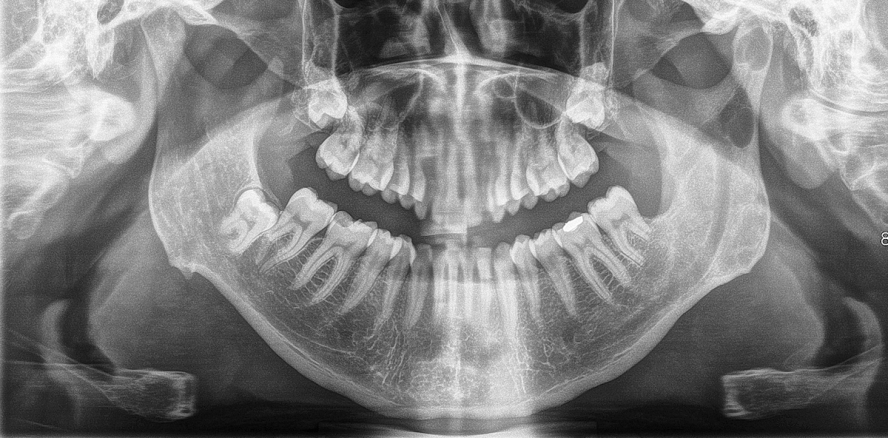

Ein 33-jähriger Patient wurde erstmals in die Abteilung für Mund-, Kiefer-

und Gesichtschirurgie des Marienhospitals Stuttgart überwiesen zur weiteren Abklärung zweier im OPG auffälligen ­zystischen Aufhellungen im Bereich des Ramus ascendens und im Kiefergelenkköpfchen links (Abb. 1). Weiterhin zeigte sich eine Resorption der distalen Wurzel des Zahnes 37 bei positiver Vitalitätsprobe. Klinisch war der Patient ohne Beschwerden. Die Anamnese ergab die Entfernung eines Weisheitszahnes und einer Keratozyste vor drei Jahren im Unterkiefer links. Zur genaueren Ausdehnungsbestimmung wurde eine weitere radiologische Diagnostik durch eine CT des Unterkiefers veranlasst. Hier konnte eine Verbindung beider zystischer Hohlräume nachgewiesen werden. Im Bereich des Kiefergelenkköpfchens war die zystische Raumforderung allseits von kortikalem Knochen umgeben (Abb. 2).